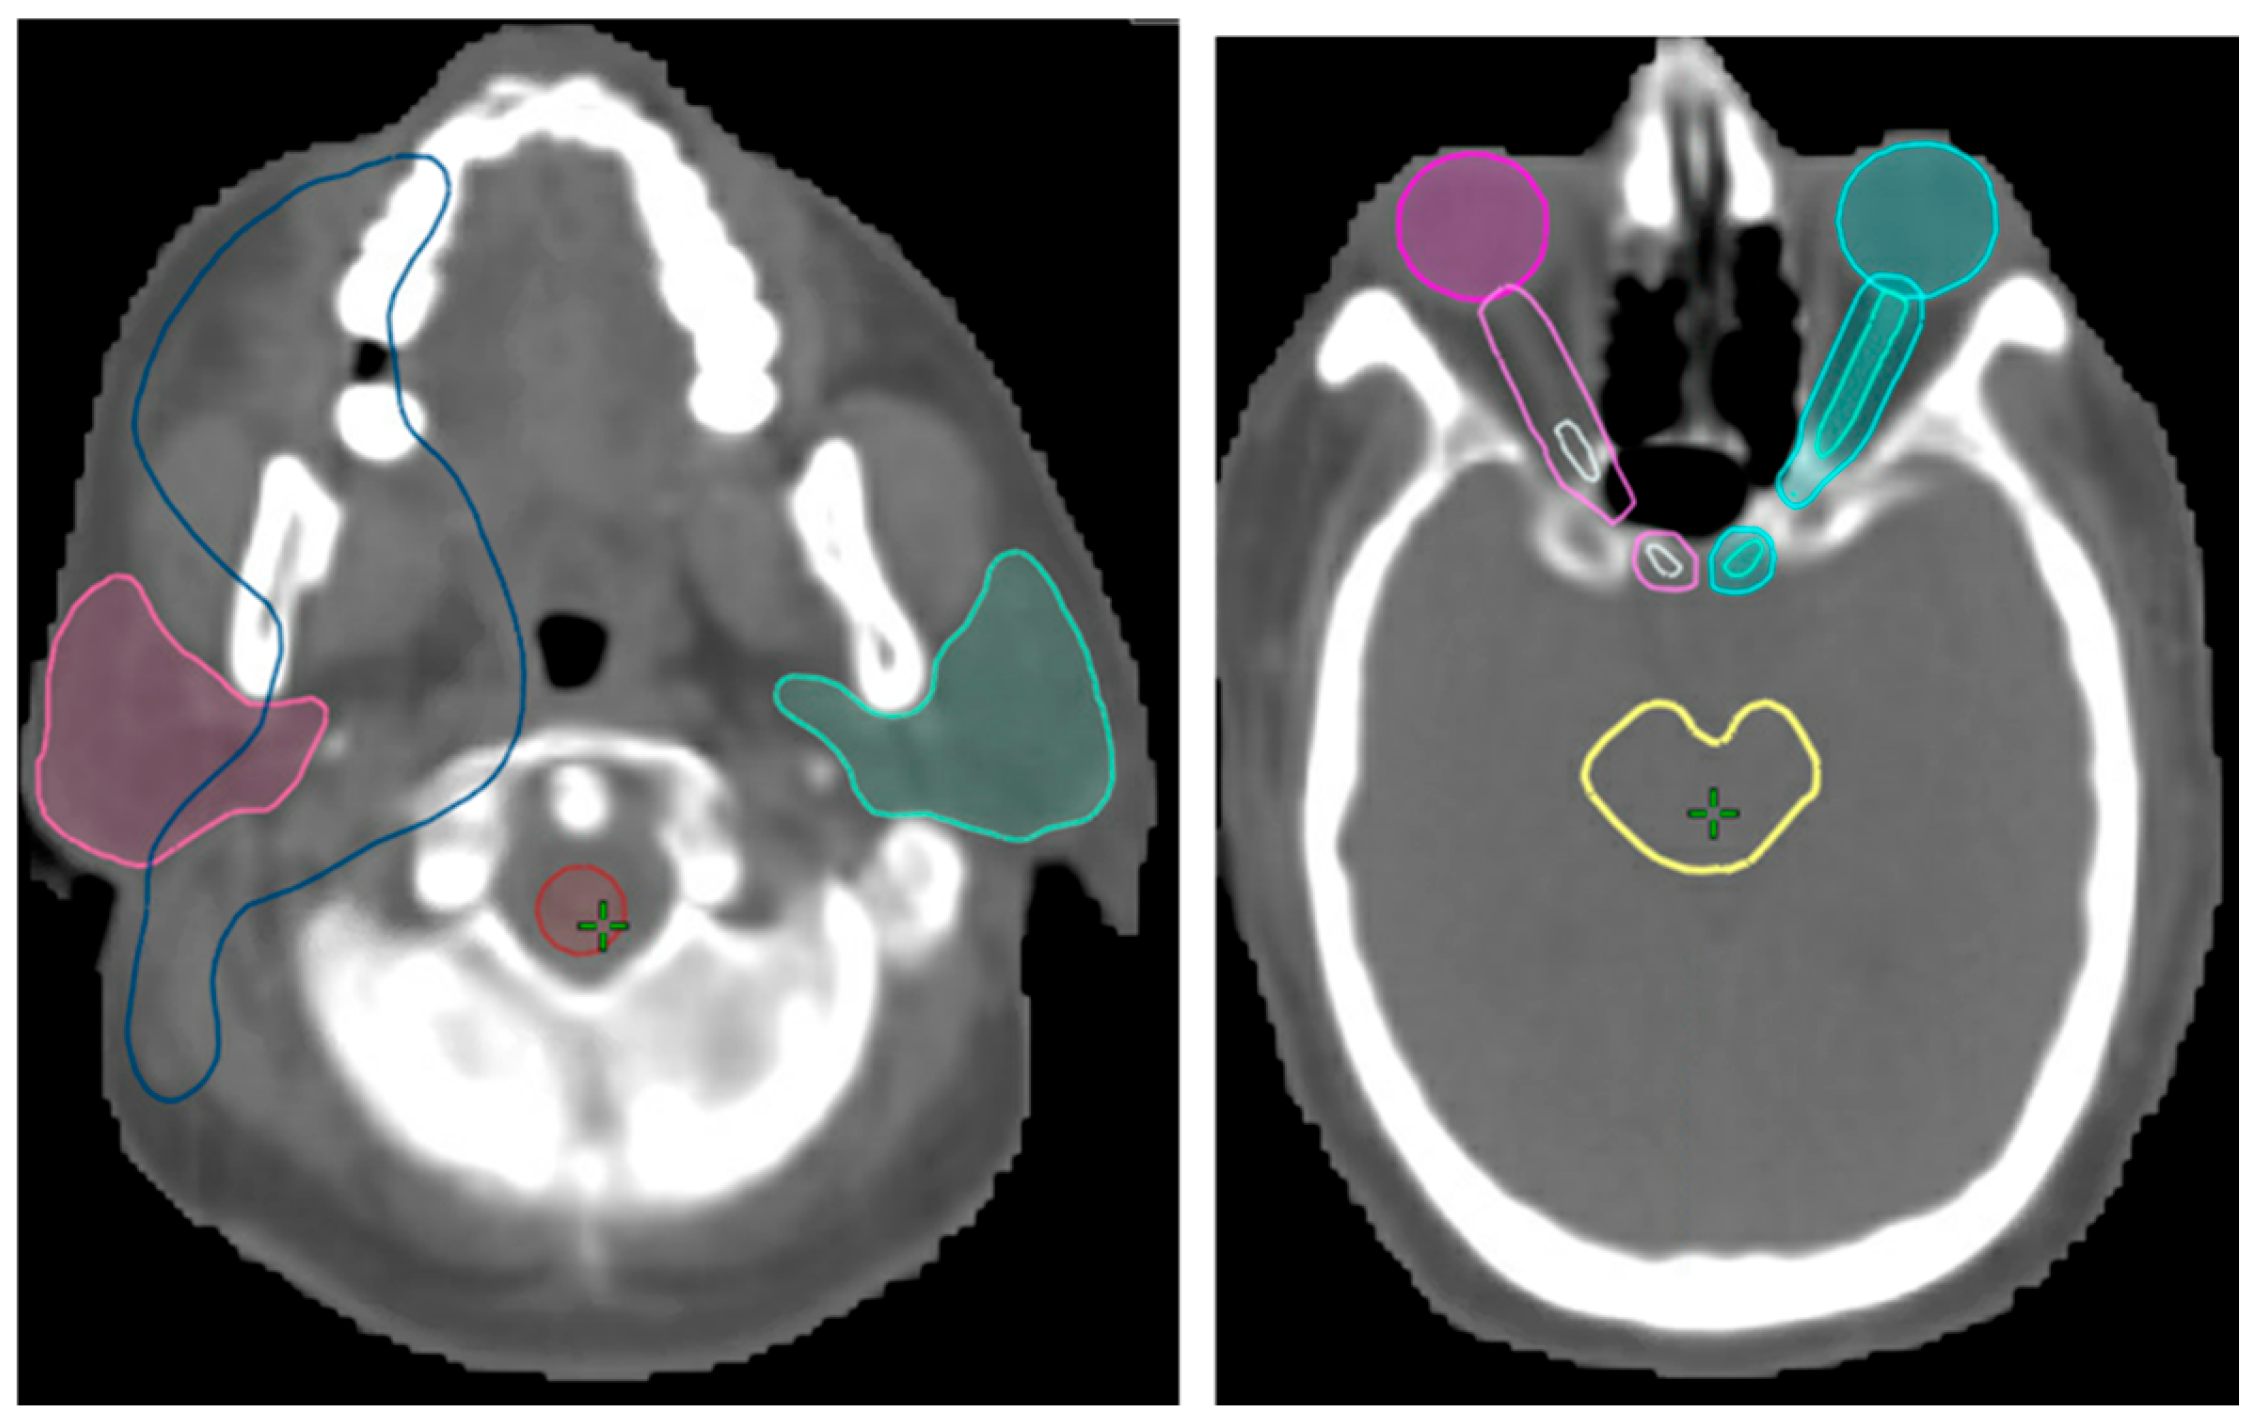

3.2. Validation of Image Registration

| Structure | Mean Warp Magnitude (mm) | Max Warp Magnitude (mm) | Mean Jacobian Determinant | Min Jacobian | Max Jacobian |

|---|---|---|---|---|---|

| Spinal cord | 1.24 | 2.69 | 1.02 | 0.96 | 1.14 |

| Parotid L | 0.76 | 1.59 | 1.07 | 0.99 | 1.16 |

| Parotid R | 1.09 | 1.52 | 0.98 | 0.9 | 1.06 |

| Larynx | 1.66 | 2.51 | 0.97 | 0.9 | 1.04 |

| Brainstem | 0.76 | 1.07 | 0.98 | 0.94 | 1.02 |

| Eye R | 0.51 | 1.07 | 1.03 | 0.97 | 1.07 |

| Eye L | 0.82 | 1.1 | 1.02 | 0.99 | 1.05 |

| Lens R | 0.38 | 0.52 | 1.04 | 1.02 | 1.05 |

| Lens L | 0.86 | 0.96 | 1.03 | 1.03 | 1.04 |

| PTV | 1.05 | 2.56 | 1.01 | 0.88 | 1.18 |